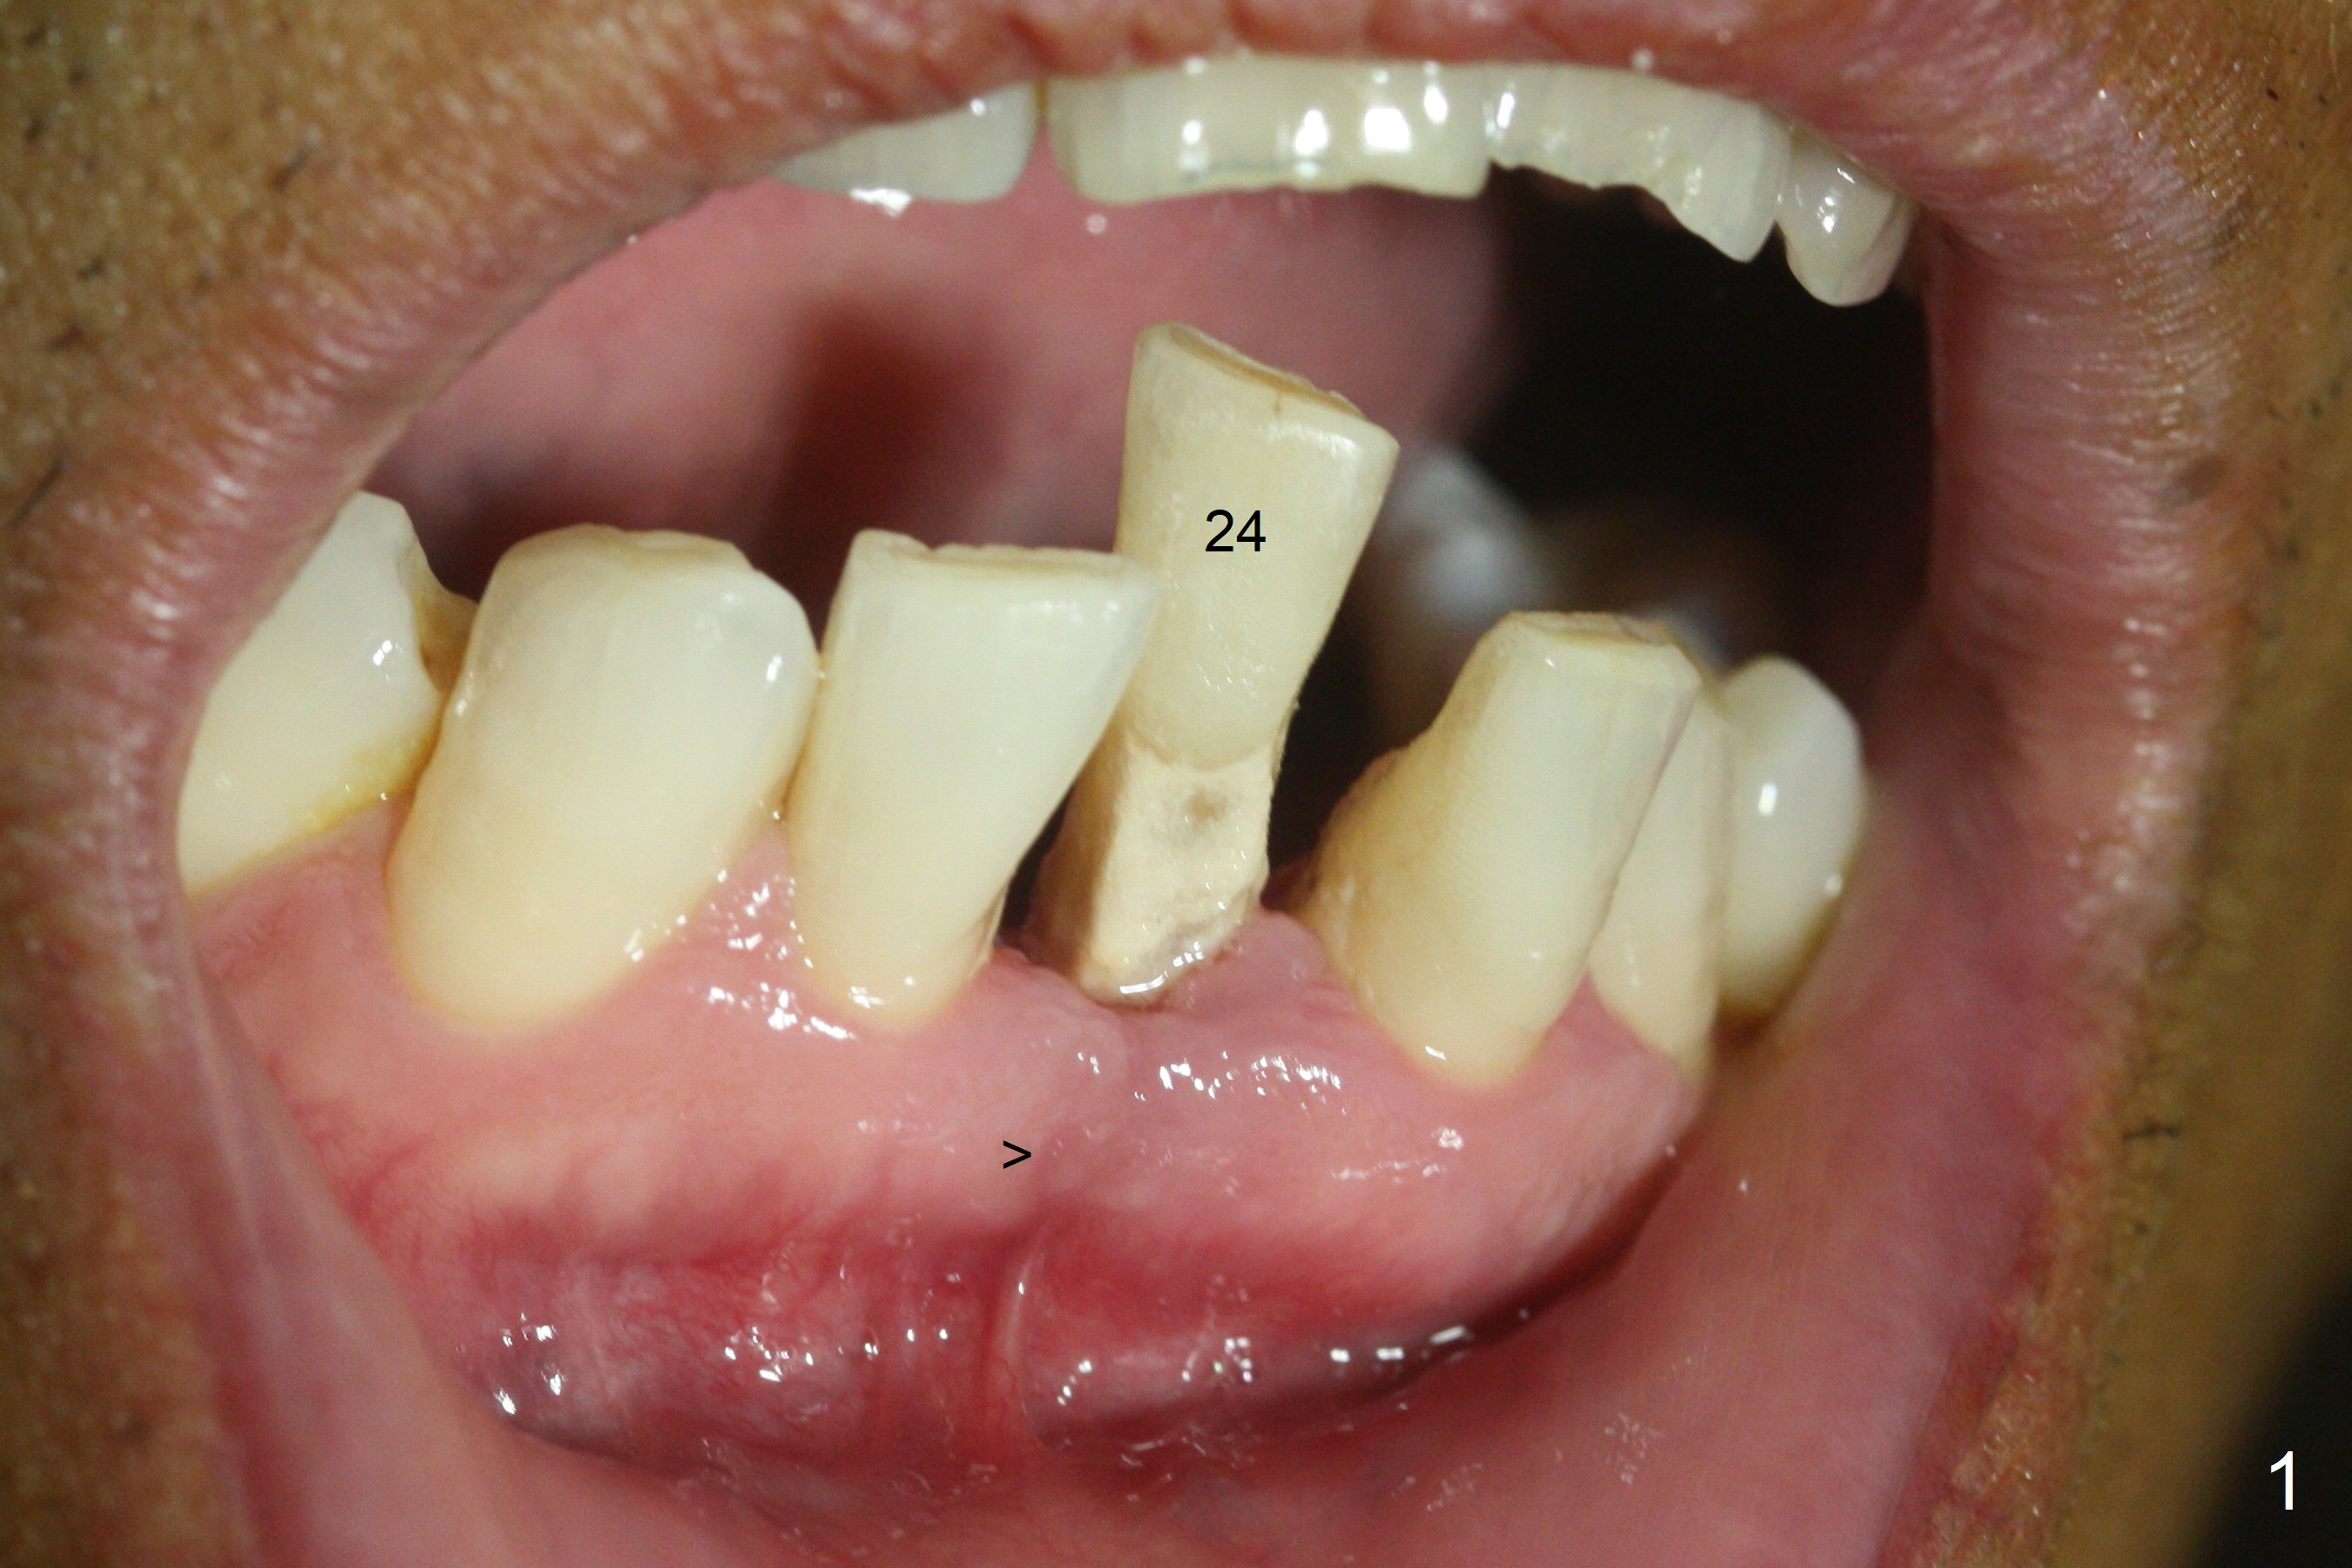

When the patient returns for implant placement 1.5 years after the last treatment (SRP), the tooth #25 has exfoliated, whereas the tooth #24 is severely displaced (Fig.1-3). In fact the buccolingual plates are found to be lost after extraction, corresponding to change in gingival color indicated by an arrowhead in Fig.1. Initial osteotomy with 1.2 mm drill is parallel to the terminal branches of the Incisive Canal (Fig.4 arrowheads). Since the gingiva is as thick as 7.5 mm (Fig.3 arrow), a 3x14 mm 1-piece implant with 4 mm cuff is placed (Fig.5); three implant threads are outside the native bone; with allograft (*) placed and the neighboring crests being coronal to the threads, the chance of periimplantitis should be remote. An immediate provisional is fabricated to contain the graft in place. Meanwhile the tooth #2 is symptomatic with crack. The top 3 threads appear to be contacted by the newly formed crestal bone 6 months postop (Fig.6 *). Bone appears to have grown into the space between implant threads 6 months post cementation (13 months postop).